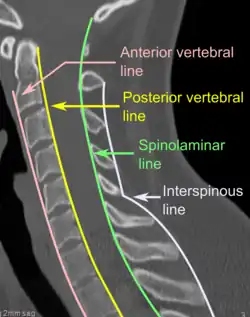

Na tomografia computadorizada ou radiografia, uma fratura cervical pode ser visualizada diretamente. Além disso, sinais indiretos de lesão pela coluna vertebral são incongruências das linhas vertebrais,[6] e/ou aumento da espessura do espaço pré-vertebral:[7]